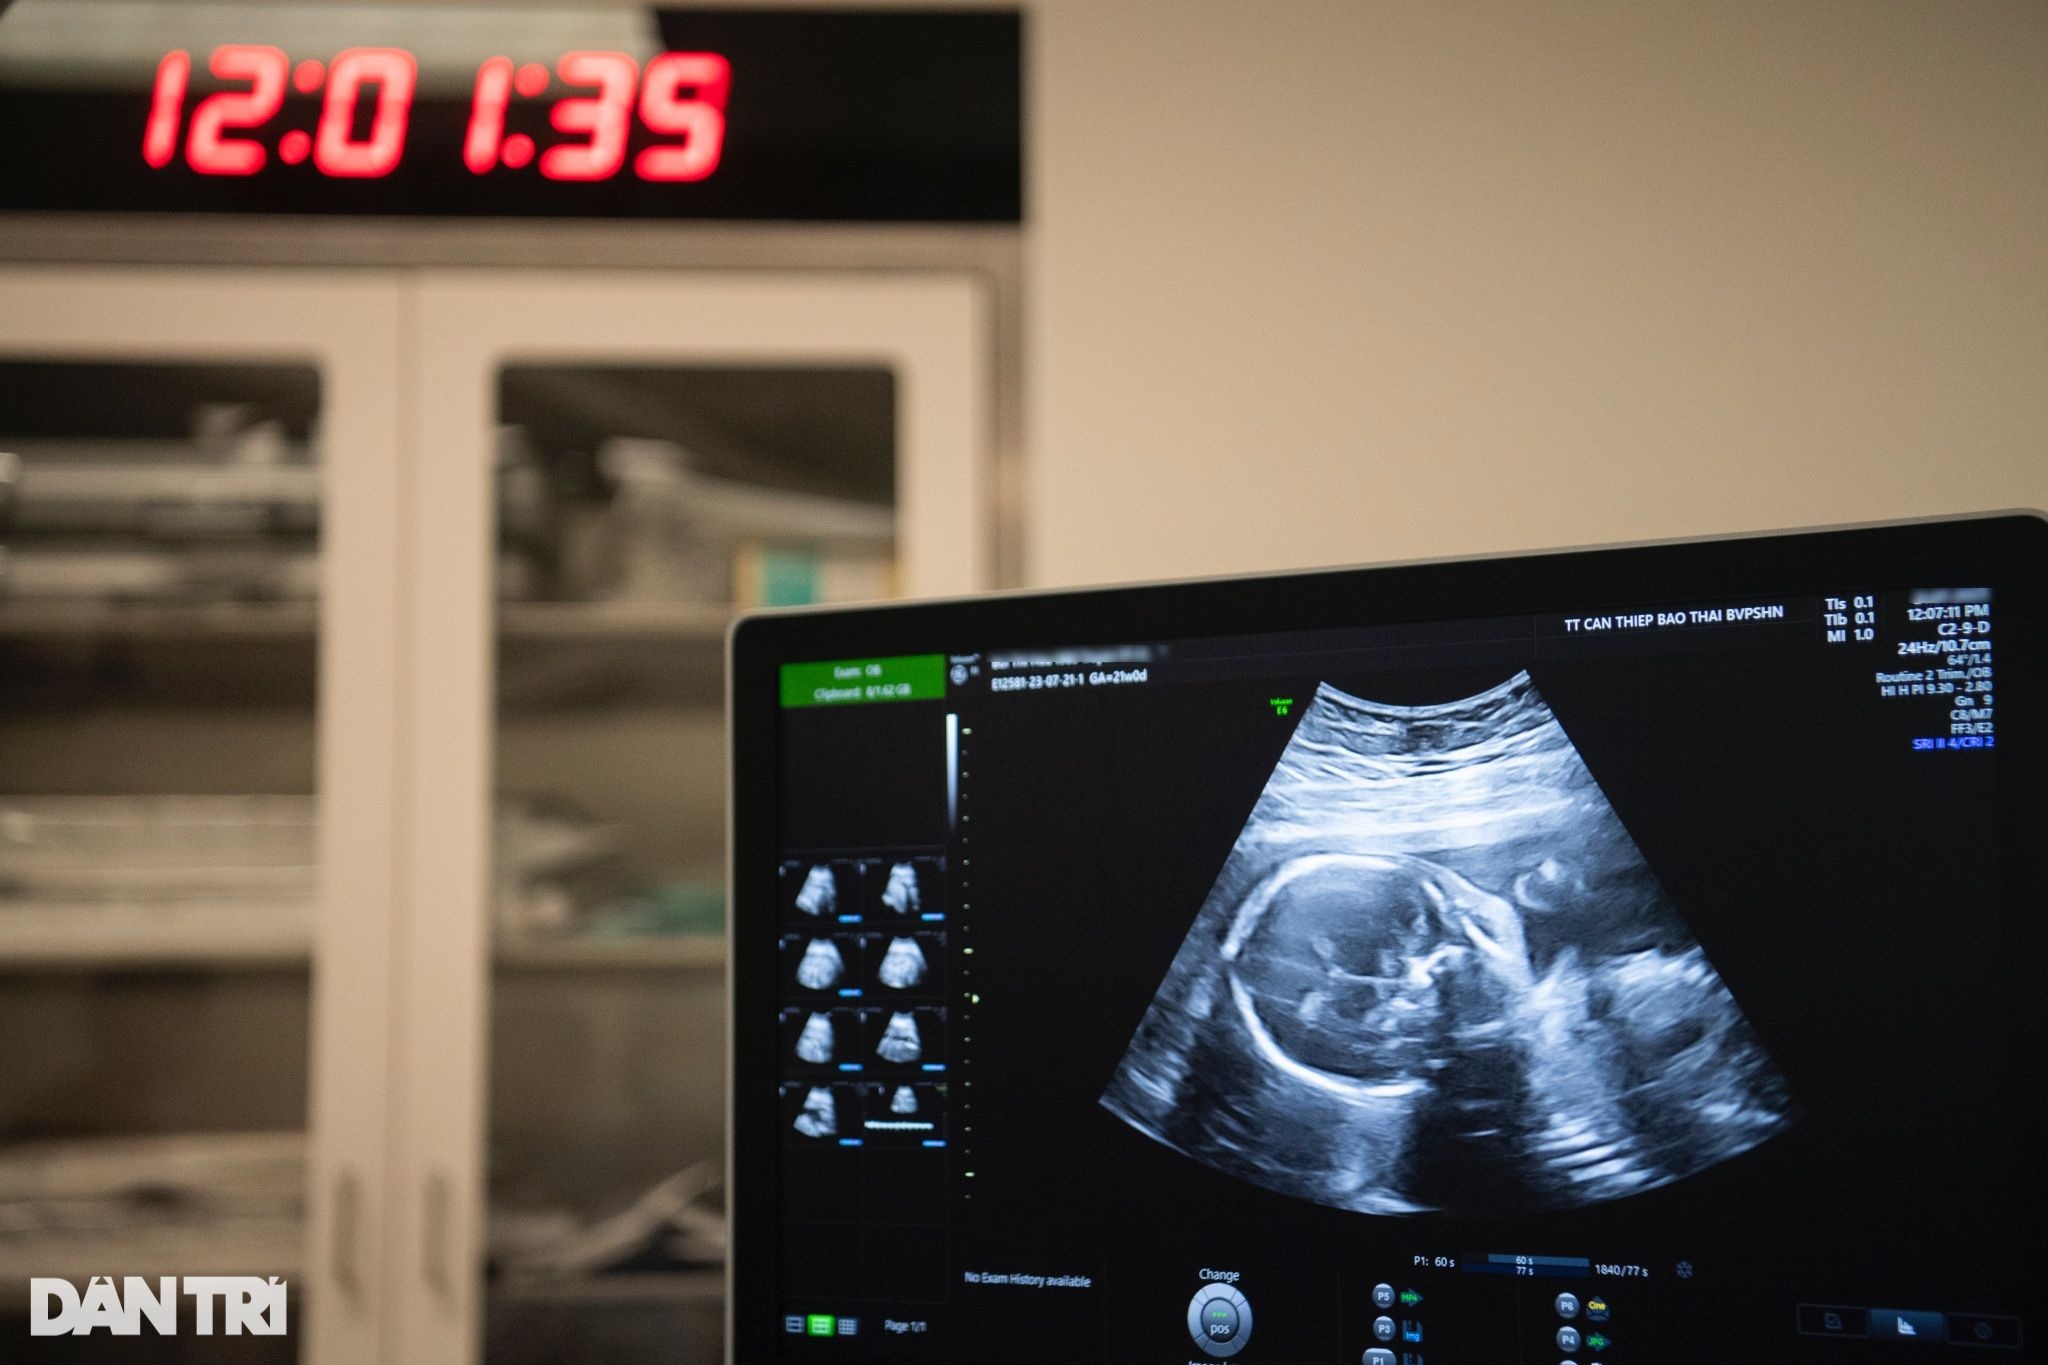

"Ngôi nhà" chật hẹp bỗng trở nên rộng rãi, em bé ngay lập tức trở nên hiếu động. Qua siêu âm có thể thấy rõ thai nhi liên tục vùng vẫy tay chân.

"Trộm vía, bé nghịch lắm, có nước ối vào là phản ứng ngay", BS Sim trò chuyện với sản phụ. Niềm vui lộ rõ trên ánh mắt chị Thoa khi cô cảm nhận ngày càng rõ từng cái đạp của con. Điều tưởng chừng như bình thường nhưng là cả giấc mơ của người phụ nữ này.

Ngắm nhìn con yêu nô đùa trên màn hình máy siêu âm, những giọt nước mắt hạnh phúc chực trào trên khóe mắt của vợ chồng chị Thoa.